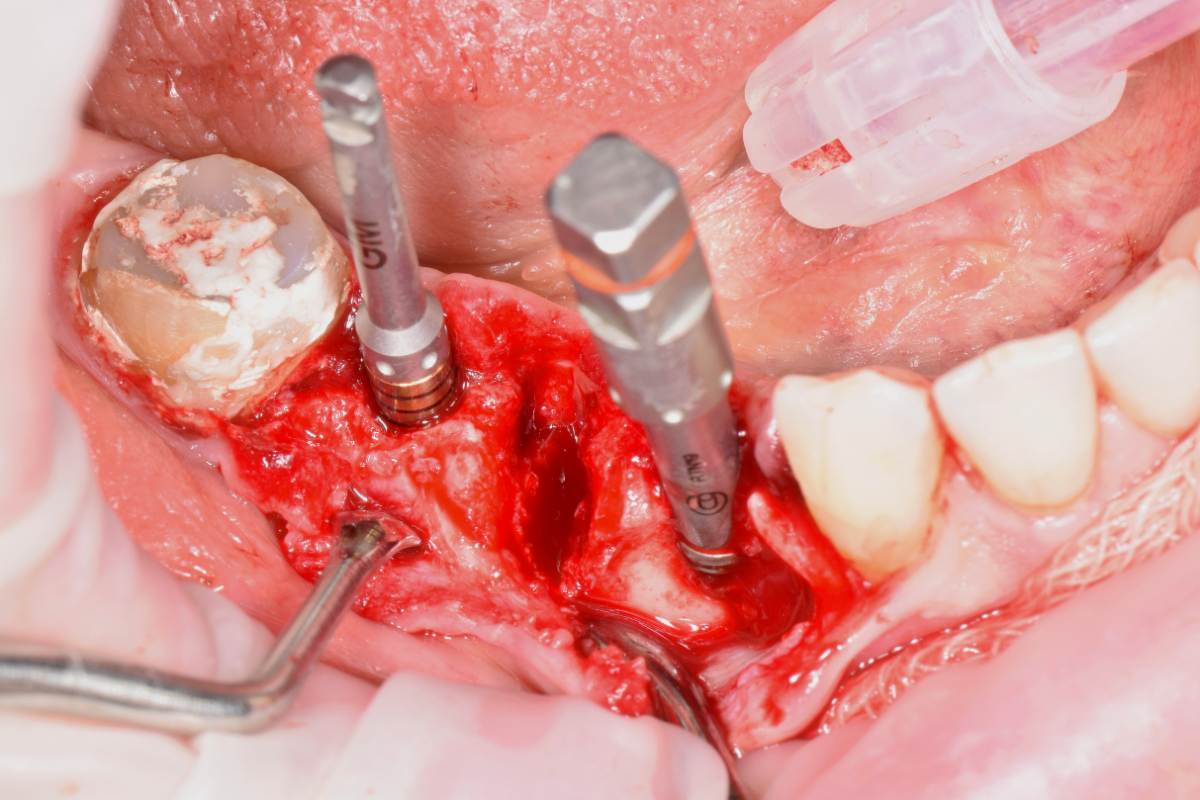

Fin Опубликовано 5 июня, 2025 Поделиться Опубликовано 5 июня, 2025 Здравствуйте коллеги. Хотел бы представить вашему вниманию первую часть кейса по восстановлению 4 сегмента. Перелом зуба 4.5 под мостовидным протезом 4.7-4.4. 4.7 решено оставить до последующего повторного протезирования При планировании имплантации вестибулярное оголение имплантата на 1.5-2мм в области 3. 4. Дефицит керотинизированной слизистой оболочки. Более глубокое положение имплантата приведет к чрезмерному количеству сзизистой оболочки в 7-8 мм. Решено не пытаться использовать ССТ с целью перекрытия оголенного имплантата а попробовать технику морковки профессора Кюри. 1 этап операции. Удаление зуба 4.5, подготовка костного ложа под имплантаты при помощи трепанов и запор костных морковок, установка имплантатов неодент 3.75х10 в позицию 4.4, 4.3х10 в позицию 4.6, ушивание. 2 этап. Создание прикрепленной слизистой. Расщепление лоскута, удаление пиноа, пересадка СДТ с фиксаций его этими же пинами. 3 этап. Открытие имплантатов с установкой ФДМ и снятие швов через 2 недели. Решил не добавлять ССТ. На данный момент ожидаем полное восстановление тканей и приступаем к этапу протезирования. Так как параллельность имплантов достаточна планирую протезировать с уровня имплантатов. 3 2 1 Ссылка на комментарий